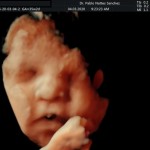

- La anatomía fetal: Diagnostico de Malformaciones Estructurales de aparición tardía (displasias esqueléticas, alteraciones cardíacas pequeñas, alteraciones de la vía urinaria y obstrucciones intestinales).